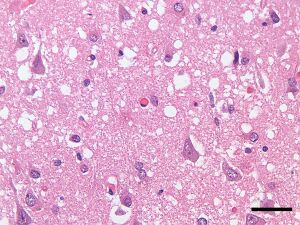

Micrograph showing spongiform degeneration (vacuoles that appear as holes in tissue sections) in the cerebral cortex of a patient who had died of Creutzfeldt–Jakob disease. H&E stain, scale bar = 30 microns (0.03 mm).

Prion diseases are marked by mental and physical deterioration that worsens over time.[5][6] A defining pathologic characteristic of prion diseases is the appearance of small vacuoles in various parts of the central nervous system that create a sponge-like appearance when brain tissue obtained at autopsy is examined under a microscope.[2][3] Other changes in affected regions include the buildup of PrPSc, gliosis, and the loss of neurons.[7]